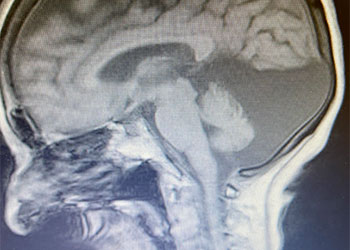

A 60-year-old woman who is otherwise healthy who presented with progressive right-sided pulsatile tinnitus for 4-6 weeks. She underwent extensive evaluation by her PCP and ENT […]

Examination: Her general and neurological examinations were normal. She was alert and oriented. Her cranial nerves were intact and her motor and sensory examinations were normal. […]